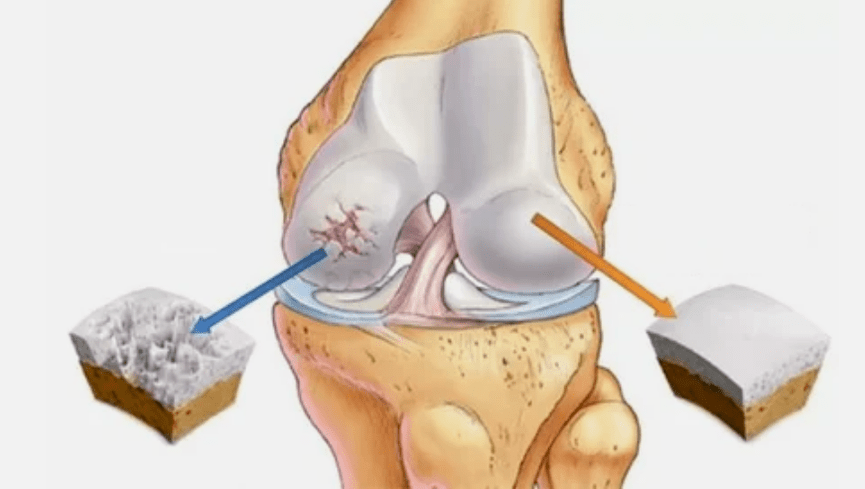

- The main lesions affect Hyaline cartilage.In the case of circulatory disorders, the decline in pathological strength occurs.It is the first step or cause, may occur.

- Hyalin coating.The thinness of cartilage leads to the replacement of its pathological tissue - bone structure.

- The abnormal growth appears on cartilage - bone.

- The violation of the natural surgery of cartilage and bone causes the overload of the healthy areas of cartilage.The destruction of joint tissues without constant treatment and leading to defects.

As the level of the disease increases, the pathological processes are still worse.Finally, all the Hyalin cartilage was destroyed.